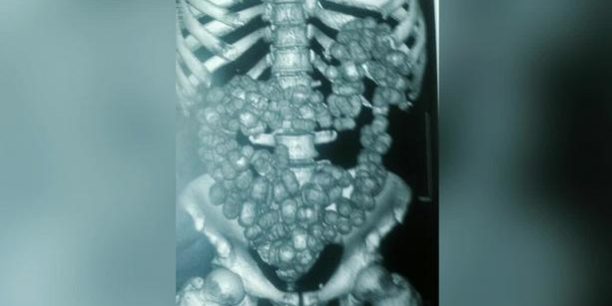

Mais les douaniers l’ont repérée. Dans sa valise, 6 kg 787g de poudre blanche. « Je savais qu’il y avait 1 kilo de cocaïne mais on m’avait dit que le reste, c’était du lait en poudre » se défend maladroitement Natou sans que l’on sache si elle tente le tout pour le tout, ou si elle est vraiment sincère, après tout. Mais qu’importe. Au tribunal de Créteil devant lequel s’est terminée son pitoyable voyage en novembre dernier, Natou a été condamnée à 30 mois de prison avec mandat de dépôt. Aujourd’hui, la cour d’appel va confirmer sa condamnation, en soulignant que d’habitude, pour une telle quantité de drogue, les peines sont beaucoup plus sévères, mais qu’on a pris en compte sa situation et son casier judiciaire vierge.